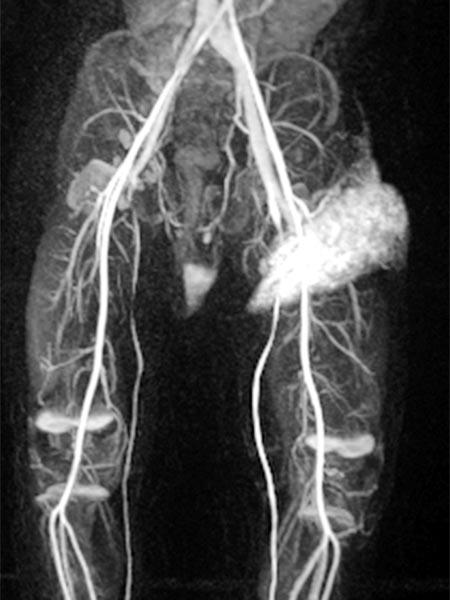

More tumor vessels with blush-like diffuse enhancement, typical of a vascular tumor / NICH. All these vessels must be selectively embolized to induce involution.

Further selective particle embolization. The embolization particles mixed with contrast medium remain in the tumor vessels.

Overview angiography via the left external iliac artery also shows no remaining perfusion of the tumor anymore, thus the tumor vascularization is successfully and superselectively completely occluded. All non-pathological arteries are preserved.